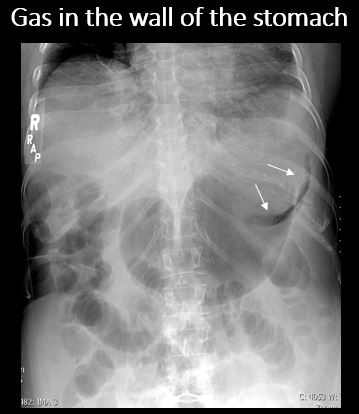

There is air in the wall of the stomach. [Yes/No]